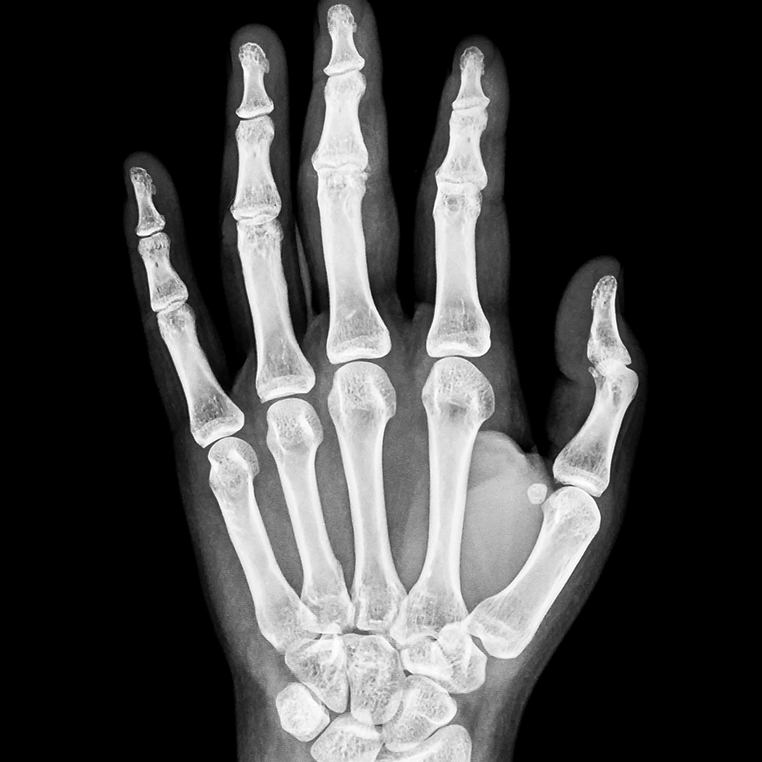

영상의학 검사

서울퍼펙트의 영상의학 검사는 먼저 방사선검사로 확인하며, 다른 질환으로 인한 증상은 아닌지 확인합니다. 손목터널증후군의 경우, 초음파 검사로 정중 신경이 눌려있는지 확인하여 진단합니다.

영상의학검사